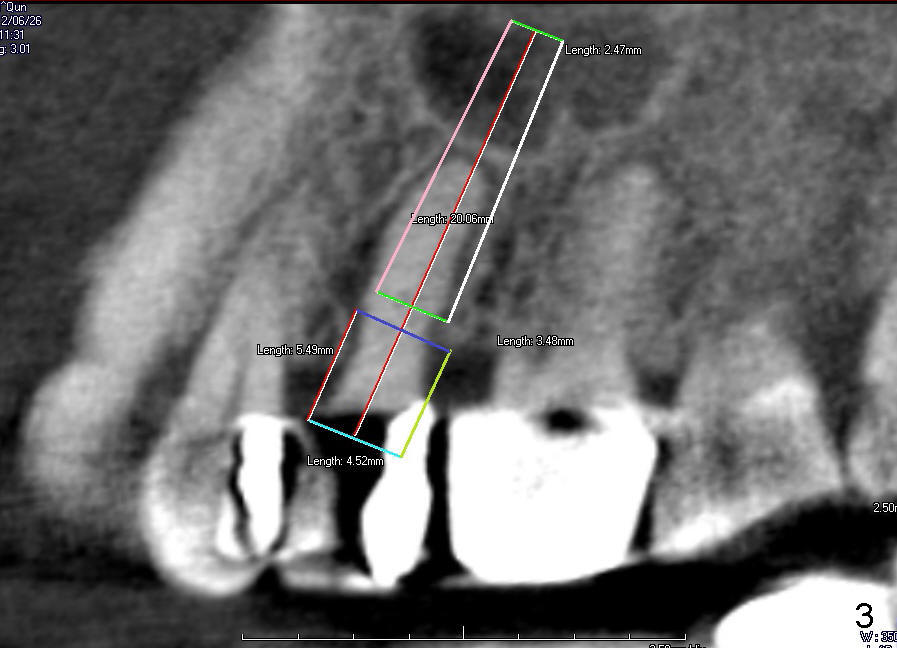

The tooth #13 has broken down to residual root now.  CBCT sagittal (Fig.1,3) and coronal (Fig.2,4) sections show designs of T (4.5x17 mm Fig.1,2) and D2 (Fig.3,4) implants.  Which is better?  It appears that sinus lift with bone graft is expected.